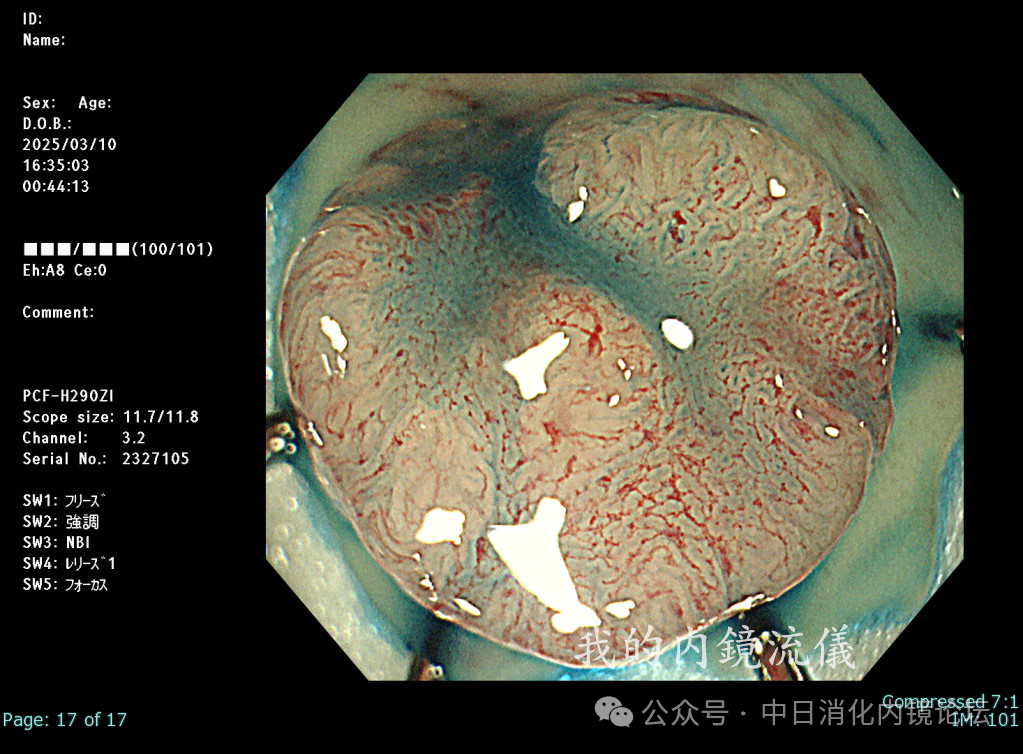

在繁忙的临床工作中按照日本消化内镜学会倡导的病变观察流程,便可事半功倍,极大地提高诊断准确性和检查效率。病变观察远景→近景→放大,白光→NBIJNET→靛胭脂 pit pattern。切除后创面确认,确保无残留,断端阴性→肛侧腹侧点墨标记→标本固定,为病理诊断以及今后可能的追加治疗提供完整精确的原始资料。